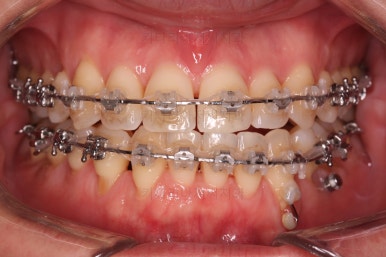

윗니도 장치를 부착했어요.

아랫니보다 해야 할 작업이 많지 않기 때문에 이렇게 시간차를 두어 진행을 했고, 이렇게 하면 교정장치가 눈에 띄는 기간이 줄어들어 환자분의 만족도는 더 올라가게 되죠.

아랫니 이 뽑은 자리는 거의 다 다물렸어요.

거꾸로 물리는 앞니도 어느 정도 많이 개선이 되었고요.

이 정도 진행되면 입매에 대해서 평가를 합니다.

아랫입술이 상당히 많이 들어갔죠? 치료의 목표가 턱뼈를 짧게 만드는 것도 아니고 교합을 맞춰주는 것인데 치료를 하다보면 얼굴모습도 좋아져요.

거꾸로 물리던 아래 앞니가 뒤로 들어가면서 튀어나왔던 아래입술이 뒤로 들어가게 되면 옆 라인이 훨씬 자연스러워지게 되죠. 턱뼈가 짧아지지 않더라도 주걱턱이 개선되어 보이는 효과를 주게 됩니다. 바로 이게 비수술교정의 핵심이라고 보시면 되요.